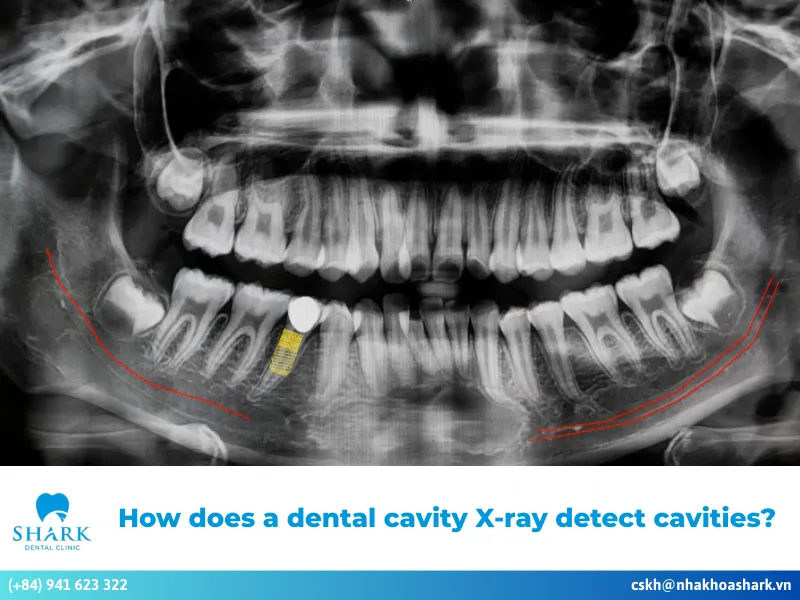

When a tooth is healthy, a dentist will see evenly colored margins on the X-ray film with moderate radiodensity. However, if an infection or dental abscess is present, the X-ray images of an abscessed tooth with an infected root canal will show several noticeable changes:

- When a tooth develops an abscess, the bone around the root tip becomes damaged. On the X-ray, this appears as a darker area compared to the surrounding healthy bone. This dark region may be oval or round, and the larger the dark patch, the more severe the abscess is. Dentists rely on this contrast when learning how to read a dental X-ray accurately.

- In healthy tooth structures, a thin line surrounds the root tip. However, when there is an infection or abscess, these margins become thicker or may appear faded. This is a warning sign that the area around the root tip is being destroyed by inflammation.

- In some cases, the dark area around the root tip appears perfectly round with a clear border, indicating that the abscess has existed for a long time. If the dark area spreads widely with an unclear margin, it may indicate a progressing infection with ongoing bone resorption.

- If the tooth has not undergone root canal treatment and the canal remains healthy, the X-ray will clearly show the root canal running from the crown down to the root tip. Conversely, if an infection is present, the canal may appear narrow or calcified, which can be observed on the X-ray film.